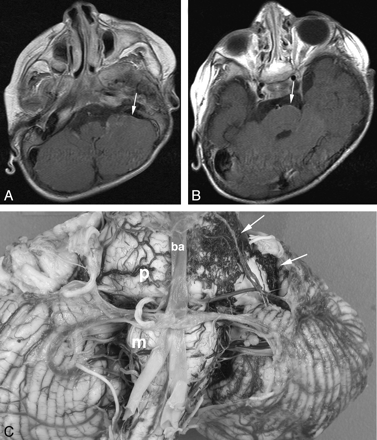

Female patient with left-sided facial PWS isolated to V1 and V2, who developed early-onset seizures and developmental delay and died at 6 years of age secondary to pneumonia. Initial MR imaging at 6 months of age (not shown) demonstrated postural plagiocephaly and mild global delay in myelination, but no features of SWS. A and B, Axial T1WI postgadolinium MR images at 32 months of age. At the time of the examination, the images were interpreted as showing no features of SWS. Retrospectively, possible subtle pial enhancement is seen overlying the left pons and cerebellar hemisphere (arrows). C, Postmortem gross pathologic specimen of the cerebellum and brain stem viewed from the ventral surface. A fine plexus of abnormal vessels is seen overlying the left side of the pons, medulla, and left cerebellar hemisphere (arrows). P indicates pons; m, medulla; ba, basilar artery.